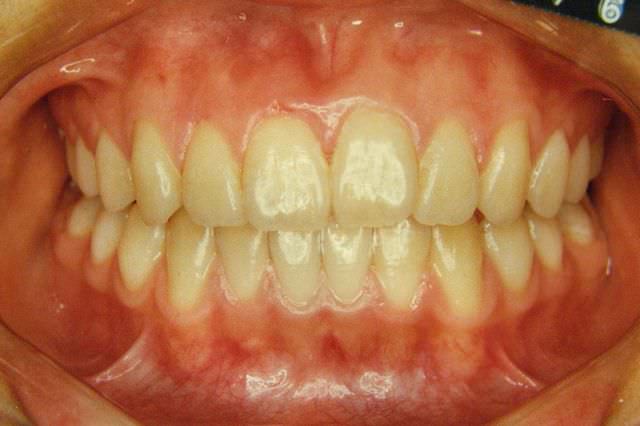

開咬 治療前

治療後

開咬 治療後

主訴 指しゃぶりをしていたせいかベロが絶えず出てしまう

診断名あるいは主な症状 開咬

年齢 14歳8ヶ月

治療に用いた主な装置 ブラケット装置 スタンダードエッジワイズ法、睡眠時FKO(アクチバトール)

抜歯部位 非抜歯

治療期間 2年4ヶ月

治療費概算 70万+月々の調整料

リスク副作用 歯の根が吸収して短くなる場合があります。

歯茎が痩せて下がる場合があります。

舌で歯を押す唇を噛む等の癖が改善されない場合は、治療期間が長引く場合があります。

定期的に通院できない、キャンセルが多い場合は治療期間が長引きます。